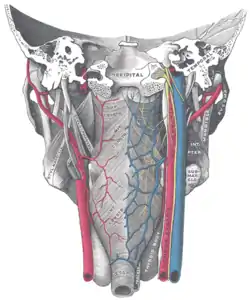

Muscles of the pharynx, viewed from behind, together with the associated vessels and nerves (middle pharyngeal constrictor muscle labeled as Mid. constr. at center) | |

Middle pharyngeal constrictor muscle Deep dissection of larynx, pharynx and tongue seen from behind

Deep dissection of larynx, pharynx and tongue seen from behind Deep dissection of larynx, pharynx and tongue seen from behind

Deep dissection of larynx, pharynx and tongue seen from behind Deep dissection of larynx, pharynx and tongue seen from behind

Deep dissection of larynx, pharynx and tongue seen from behind